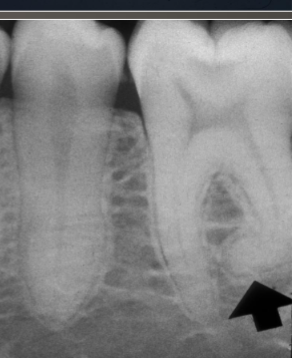

dilaceration

what is shown here?